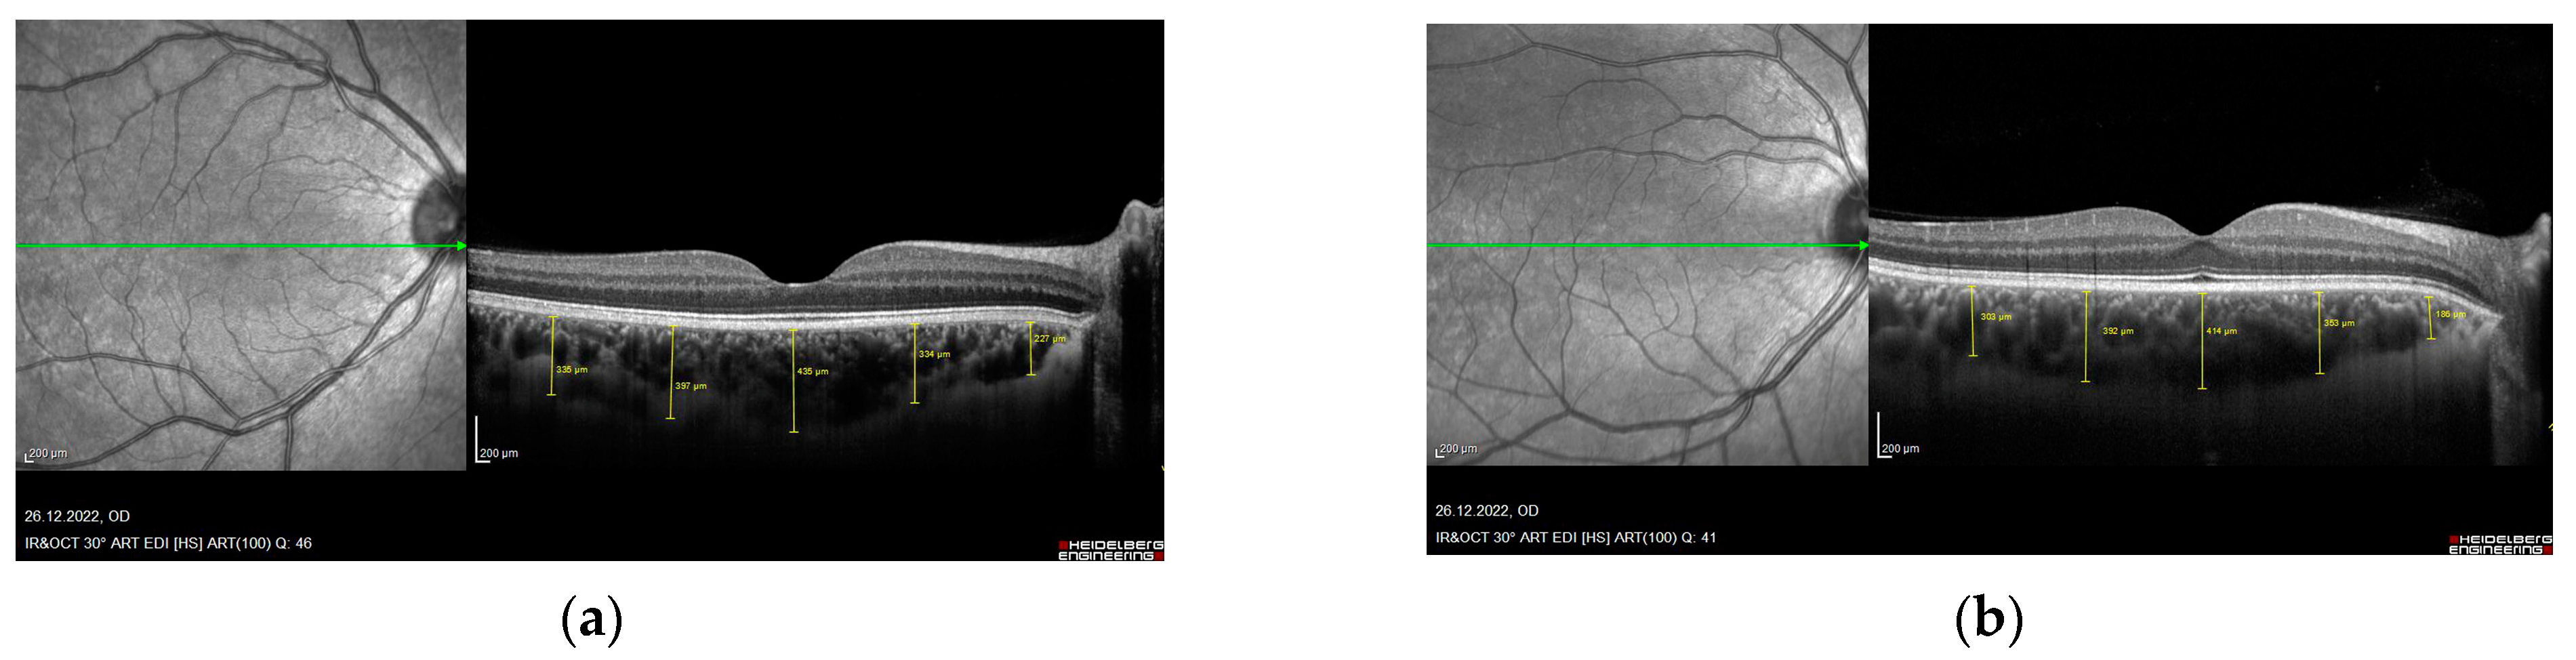

The RNFL and choroid were imaged with undilated pupils using spectral domain OCT (Spectralis, Heidelberg Engineering, Heidelberg, Germany). Quality control for all scans was performed before enrollment. To improve the visualization of the choroid, the instrument’s enhanced depth imaging mode was used in combination with automatic real-time eye tracking and frame averaging. Each subject was imaged by both ophthalmologists, and the two values, captured by two different ophthalmologists, were averaged for analysis. All differences between measurements taken by the blinded ophthalmologists for each subject were within 10% of the mean value. All examinations were performed between 09:00 and 12:00 a.m. to exclude diurnal variations [13]. Right eye values were used for statistical analyses. Retinal nerve fiber layer thickness was determined from the optic nerve head scan. A volumetric scanning protocol was used, imaging a 15 by 15 region surrounding the optic nerve head (circle scan size 3.4 mm). Choroidal thickness was measured manually by marking the distance between the outer margin of the retinal pigment epithelium and the choroid-sclera junction. In addition to subfoveal choroidal thickness, choroidal thickness was also measured 1.500–3.000 µm nasal to the fovea and 1.500–3.000 µm temporal to the fovea (Figure 1).

Figure 1.

Optical coherence tomography image showing macular choroidal thicknesses in five different locations. (a) XFG, (b) XFS.